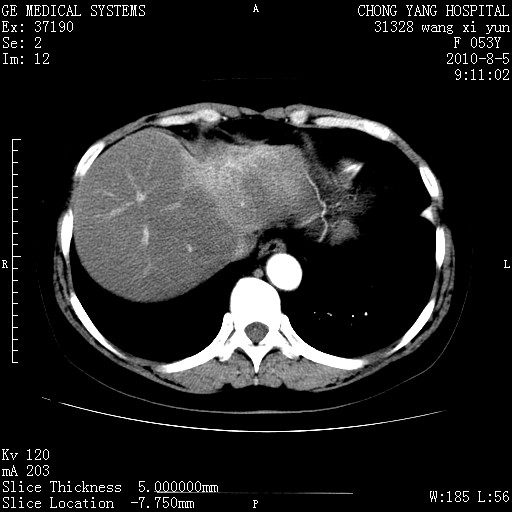

标题: CT28214:F41Y 血尿二十天,建议盆腔平扫加增强。

胆管细胞ca?

1)考虑肝左叶胆管细胞癌。2)脂肪肝。

支持胆管细胞ca。